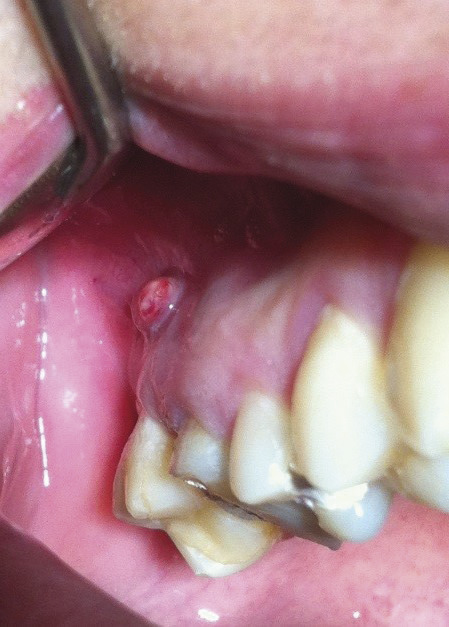

Les foyers infectieux d’origine dentaire sont secondaires à une pathologie dentaire pure ou à une pathologie du tissu de soutien (parodonte). Le plus souvent, la cause est une nécrose de la pulpe dentaire secondaire à une carie ou à un traumatisme. En l’absence de traitement, le risque d’un abcès dentaire est l’extension de l’infection par contiguïté aux dents adjacentes, la diffusion dans les tissus mous (cellulite faciale d’origine dentaire) ou la fistulisation (comme ici, par exemple, au niveau de la table osseuse externe vestibulaire).

La fistulisation survient au stade chronique de l’infection après des mois, voire des années, d’évolution. Elle peut se faire au niveau de la muqueuse (95 % des cas) ou de la peau. Le patient néglige le plus souvent la lésion, qui apparaît à distance de l’épisode aigu et est asymptomatique. Après avulsion de la dent en cause et curetage soigneux de la lésion infectieuse, le patient a bénéficié d’un traitement par bains de bouche et antibiotique (amoxicilline-acide clavulanique 1 g 3 fois par jour pendant 7 jours). L’évolution a été favorable. L’examen post-avulsionnel de la dent n° 16 (photo 3 ) a montré qu’une perforation instrumentale, lors d’un traitement radiculaire de la racine disto-vestibulaire, était à l’origine du foyer infectieux.